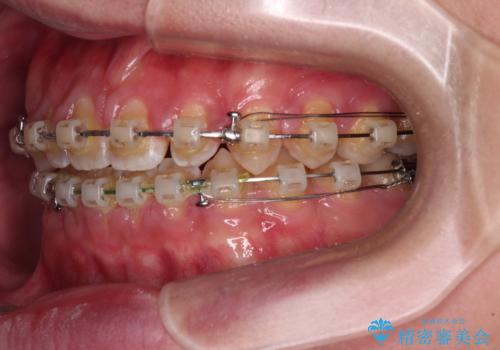

- クリアブラケット

- 3年2ヶ月

- 10-30回

舌の突出癖がなかなか改善されず、治療期間は当初予定よりも大分長くなりました。

装置除去を予定していた日に、油断されたのか1mmほどのスペースを作ってしまったため、除去が3ヶ月延長されたことで、舌のトレーニングの重要性を理解していただきました。